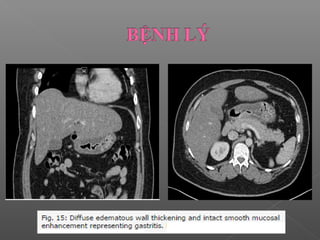

 Viêm dạ dày mạn tính:

Biểu hiện: dày thành dạ dày < 5mm, lớp niêm mạc

ngấm thuốc đều, lớp mỡ quanh dạ dày bình thường,

không có nốt ngấm thuốc bất thường

Thành dạ dày ≥ 1 cm cần nghĩ đến u.

 Viêm dạdày mạn tính: Biểu hiện: dày thành dạ dày < 5mm, lớp niêm mạc ngấm thuốc đều, lớp mỡ quanh dạ dày bình thường, không có nốt ngấm thuốc bất thường Thành dạ dày ≥ 1 cm cần nghĩ đến u.